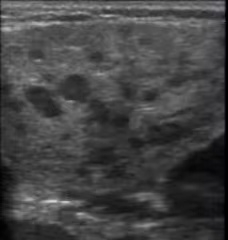

●唾液腺评估(腮腺+颌下腺):超声可观察腺体形态、大小及内部回声。干燥综合征患者典型表现(图2)为腺体弥漫性增大,内部回声不均匀,可见多发低回声区,血流信号增多,这些特征能直观反映腺体炎症及纤维化程度。

▲图2:腮腺体积增大、回声不均匀,可见散在的低回声区